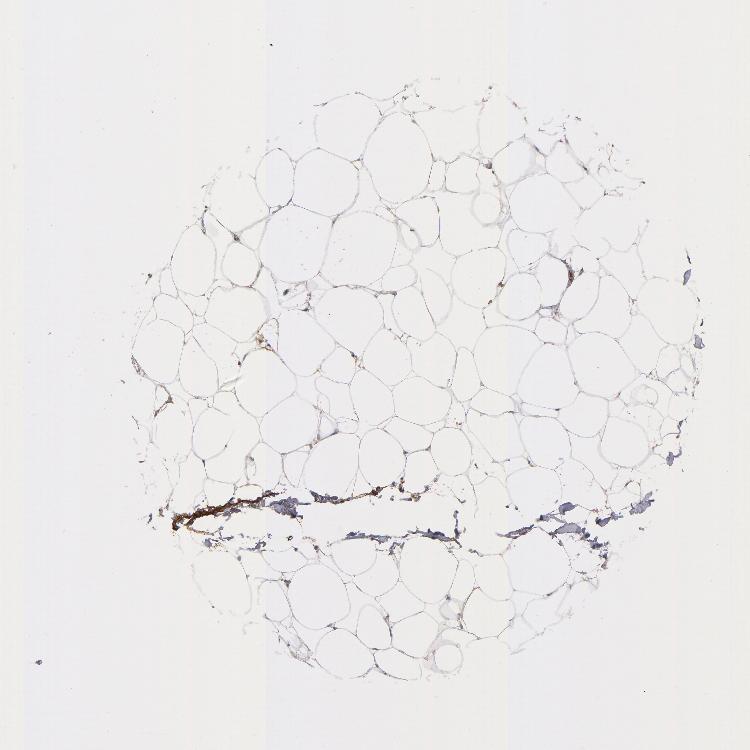

ADIPOSE TISSUE - Antibody stainingi

Antibody staining in the annotated cell types in the current human tissue is reported as not detected, low, medium, or high, based on conventional immunohistochemistry profiling in selected tissues. This score is based on the combination of the staining intensity and fraction of stained cells.

Each image is clickable and will lead to virtual microscopy that enables deeper exploration of all samples and also displays staining intensity scores, fraction scores and subcellular localization as well as patient and tissue information for each sample.

Antibody HPA003016Antibody HPA074619

Adipocytes LowNot detected